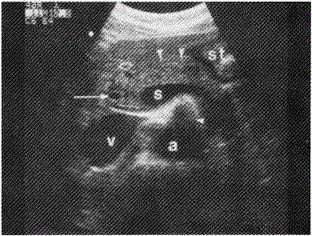

男性,30岁,健康体检,超声图像中箭头所指为

超声图像中箭头所指为胆总管。